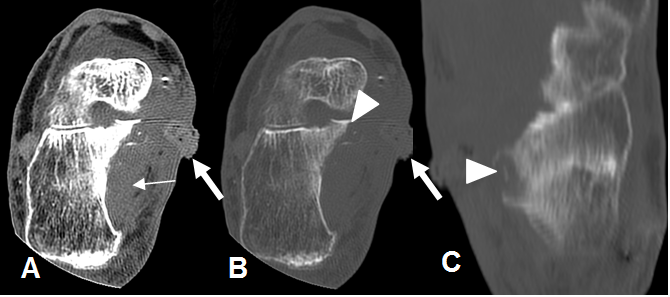

Fig 128 A. Osteomielitis del calcáneo.

A: TAC axial en ventana de tejido y B: en ventana de hueso. Cambios inflamatorios en los tejidos blandos (Flecha delgada), con orificio de fístula medial. (Flecha gruesa).

C: TAC reconstrucción coronal. Erosión del calcáneo, por osteomielitis. (Punta de flecha).